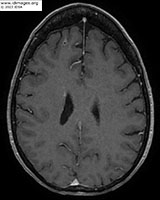

The patient suffered a fall and underwent head CT scan which demonstrated abnormalities. A subsequent MRI of the brain demonstrated numerous small ring-enhancing lesions throughout both cerebral hemispheres (Figure 3). A bronchoscopy with BAL demonstrated 97 cells, 71% neutrophils, aerobic, anaerobic, fungal, AFB, Legionella cultures, Pneumocystis jirovecii PCR and cytology were all negative. No biopsy was performed. Cell free DNA sequencing of plasma (Karius TestTM) was sent. Patient expressed preference to complete workup as an outpatient when a nodule was felt on her right calf. A new area of pain and swelling had emerged which on vascular ultrasound appeared to be an abscess. An MRI of the tibia/fibula demonstrated a 1.5x1.4cm peripherally enhancing lesion in the medial gastrocnemius muscle concerning for intramuscular abscess (figure 4). Interventional radiology performed aspiration of the abscess.

- Figure 3: MRI brain with and without contrast.

Patient treated with ceftriaxone IV 2gm every 12 hours for 3 months and sulfamethoxazole-trimethoprim 800-160mg 1.5mg tablets by mouth every 12 hours for plan of at least 12 months of therapy. Repeat CT chest 1 month (Figure 8a) and 6 months (Figure 8b) after start of antimicrobial therapy showed marked improvement in the cavitary consolidation in the right upper lobe. MRI brain after 6 months of treatment with near complete resolution of prior infection (Figure 9b).

- Figure 9: MRI brain after 6 months of treatment.